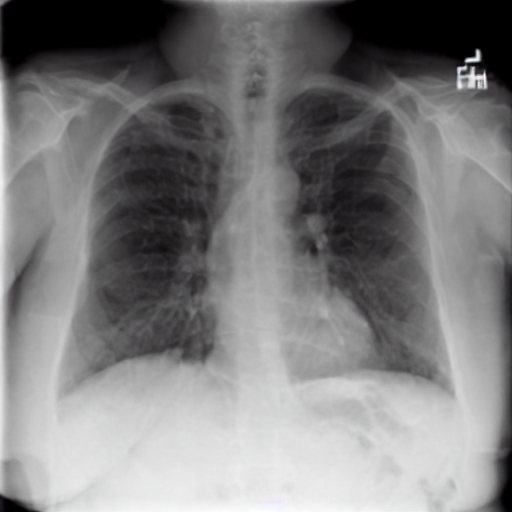

We therefore illustratively test our model in regard to its latent capability to induce disease in specific locations through the simple expedient of conditioning on positionally-indicative text. The results may be seen in figure 7 for the case of localized lung opacity (lung opacity being chosen because it is both diffuse and generally specific to one or other lung). The respective condition texts are “large lung opacity on the left” and “large lung opacity on the right”.